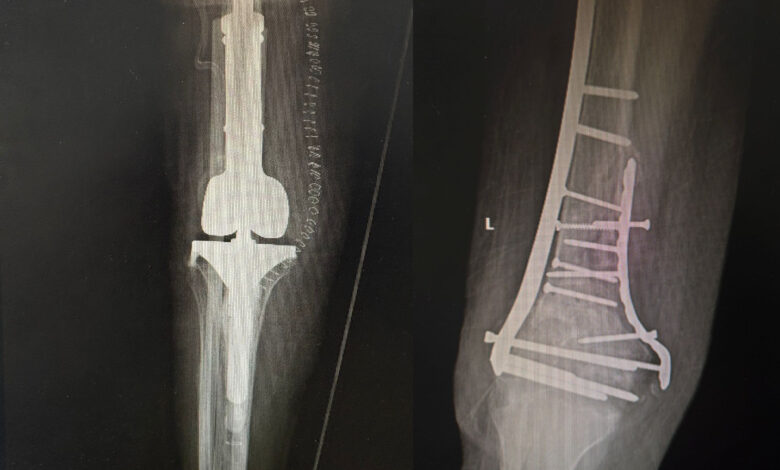

نجح فريقٌ متكامل من جراحي العظام على مستوى تجمع المدينة المنورة الصحي، بقيادة وحدة جراحات الركبة والمفاصل الصناعية في مستشفى الملك فهد، في إجراء عملية جراحية معقدة ونادرة لسيدة في العقد الثامن من العمر، كانت تعاني لأكثر من عام من كسرٍ قديم في أسفل عظمة الفخذ، نتج عنه عدم التحام العظم وفقدان القدرة على المشي.

وأوضح التجمع أنه وبعد دراسة الحالة بشكلٍ مكثف، ومناقشة الخيارات العلاجية المناسبة، تقرر إجراء عملية استبدال الجزء البعيد من عظمة الفخذ مع تغيير مفصل الركبة (Distal Femur Replacement)، وهي من العمليات التخصصية الدقيقة التي تُجرى للحالات المعقدة، وتتطلب مستوىً عاليًا من الخبرة والدقة في التخطيط والتنفيذ، وتُعد من الحلول الجراحية المتقدمة التي تُمكّن المرضى من استعادة القدرة على الحركة عند فشل الطرق العلاجية التقليدية.

وأشار إلى أن العملية – ولله الحمد – تكللت بالنجاح، حيث تمكنت المستفيدة من الوقوف والمشي في اليوم التالي مباشرةً، في نتيجة تعكس الكفاءة العالية والخبرة المتقدمة للفريق الجراحي، وتؤكد جاهزية مستشفى الملك فهد للتعامل مع الحالات الدقيقة والنوعية وفق أعلى المعايير الطبية.